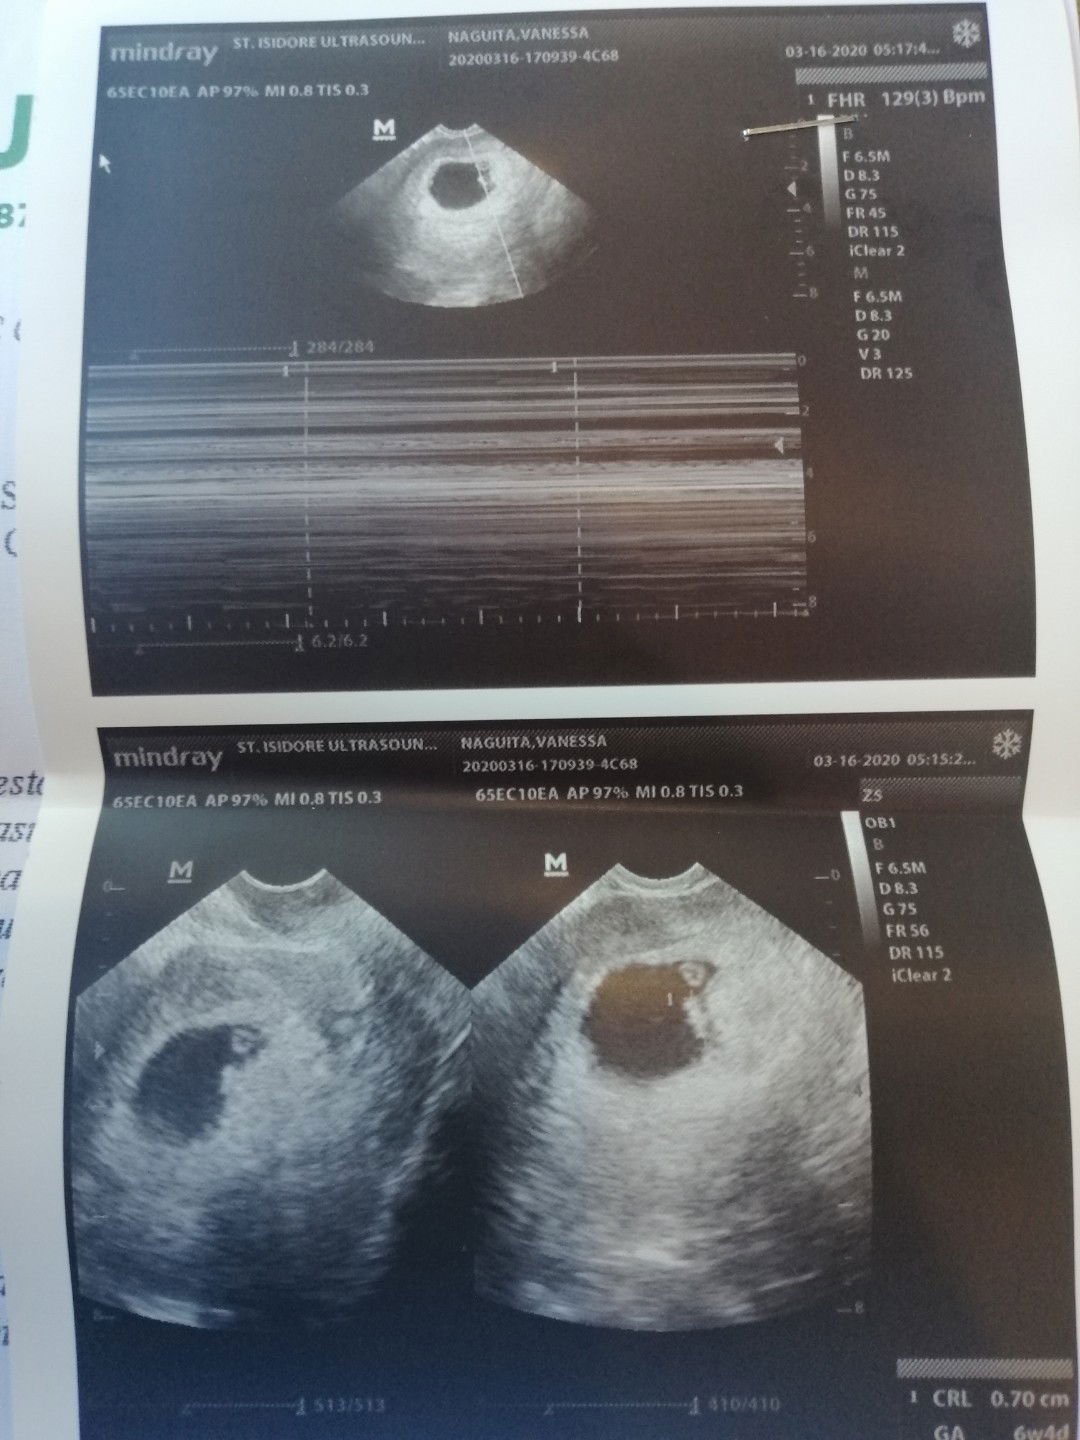

hello guys.. im a second time mom now with 7week bby inside .. my 1st born is illegitimate child he is now 8y.o.. suddenly I meet a wrong guy again who is the father of my 2nd child, and he said he is not yet ready for the responsibility.. so what he did is he give me medicines to abort the child and went to "hilot" to assure.. but all of those wasn't effective so I decided to keep the bby in spite of many what ifs.. (about my work, family, and the people around me should criticised and judge me cOz due to my situation). then last Friday, March 13, 2020 there's a blood in my panty liner on the next day I went to the ob for check up.. the doctor said its not normal so I was alarm what happen inside she advise me for tvS. and the result is I have a minimal subchorionic hemmorage.. the heartbeat is okay.. the doctor gave me PROGESTERONE.. I need some advices if it affects my bby.. is there some defects to my bby?